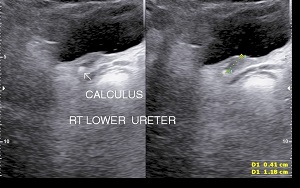

Upper ureteric & lower ureteric calculi can be visualized by sonography however middle ureteric calculus may not be visualized due to overlying gas shadows.

• Ureteric Calculi: